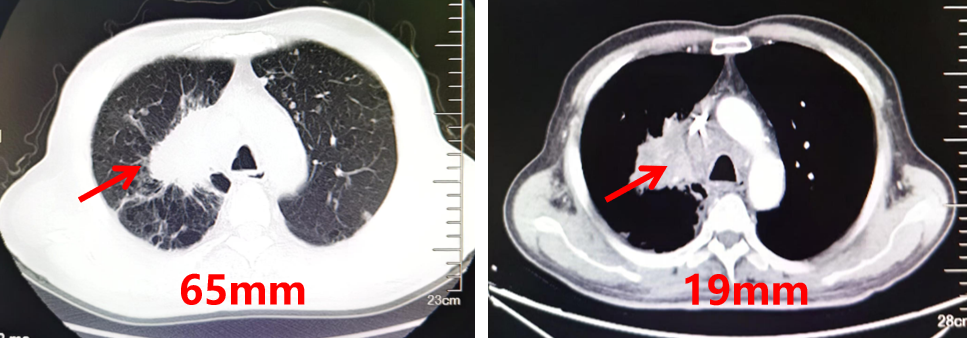

胸部CT:右肺示团块状不均匀软组织密度影,最大直径约65mm。

图1.胸部CT结果(2024.08)